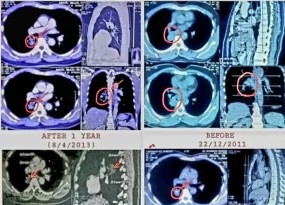

The Pioneer Patient: 12 Years of Defying Deadly Lung Cancer

The First Lung Cancer Survivor to Use ECCT on a Doctor’s Advice

In late 2011, Mr. Abdulmalik was diagnosed with advanced Stage 3-4 Adenocarcinoma Lung Cancer, a condition where over 80% of patients typically do not survive past five years. His pulmonologist, recognizing that conventional chemotherapy would offer little benefit against the significant side effects, became the first physician to boldly recommend the then-experimental ECCT (Electro-Capacitive Cancer Therapy). Mr. Abdulmalik agreed to be the first lung cancer patient to test the device. The results were historic: within one month, his bloody coughs ceased and the tumor mass shrank by half. Over a decade later, he remains healthy and active in his 60s, having turned a 2.5-year life expectancy into more than 12 years of survival.